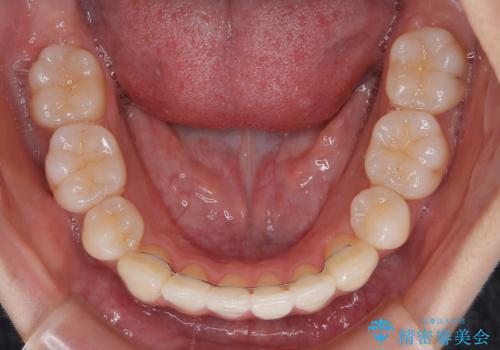

1. 抜歯矯正の軽度後戻りを解消 インビザライン矯正の治療前

2. 抜歯矯正の軽度後戻りを解消 インビザライン矯正の治療中

3. 抜歯矯正の軽度後戻りを解消 インビザライン矯正の治療後